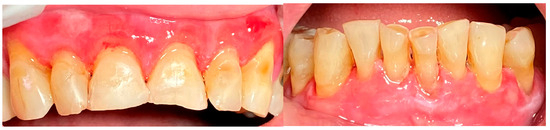

2.1. Clinical Case 1—Mucous Membrane Pemphigoid (MMP)